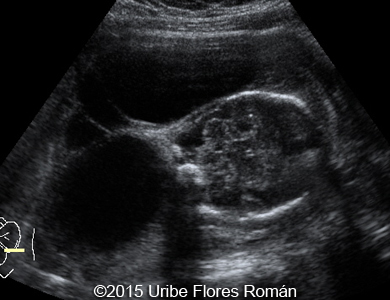

Cystic hygroma, hydrops, 28 weeks

Following images show a case of cystic hygroma, hydrops, and severe oligohydramnios that was seen in a fetus of a 26-year old woman (G2P1). She was sent to our office at 28 weeks. The newborn had been delivered via cesarean section and died shortly after delivery. The findings were confirmed but the autopsy was refused by the parents.